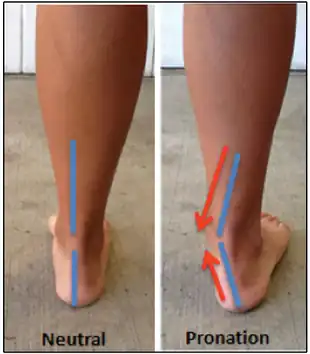

During the loading phase of the running and walking cycle, the ankle and foot naturally pronate and supinate by approximately 5 degrees.[13] Excessive pronation of the foot (over 5 degrees) in the subtalar joint is a type of mechanical mechanism that can lead to tendinitis.[12][13]